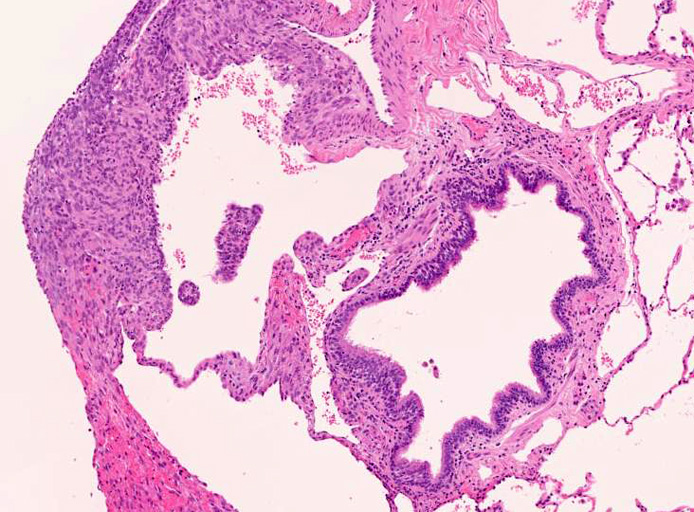

LAMの組織病理

LAMの肺病変

嚢胞周囲または肺血管, リンパ管, 細気管支にそうLAM cellの浸潤, 集簇を特徴とする。LAM cellには2種類が認められ, 小型紡錘形細胞と細胞質の豊富な類上皮様細胞があり, 紡錘型は主に集簇巣の中心に存在し増殖能が高い。 類上皮様LAM cellは辺縁部に多く, 増殖能は低いがHMB45を強く発現している。

嚢胞形成はLAM cellの増殖と関連しており, 細胞が産生するmatrix metalloproteinases(MMPs)による組織破壊によるらしい。